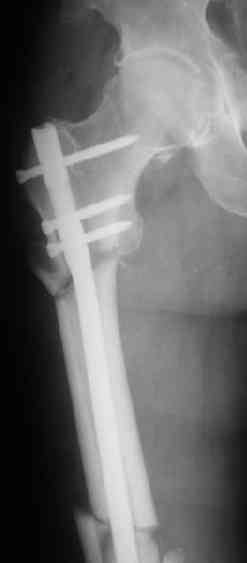

Судя по уровню перелома, винты в шейку избыточны, подойдет и диафизарный гвоздь. Все, что нужно, это тиски и труба. Загнуть сразу ниже отверстий градусов на 8-10, и вся недолга. Последние годы у нас это рутинная практика. Предызогнутые еще с завода гвозди неудобны тем, что они уже правый-левый.

Согласен, что закрытый реостеосинтез с рассверливанием и коррекцией оси - это то, что надо. Мы бы ввели в центральный отломок статических 2-3 винта, и один динамический винт в дистальном отломке.

Вот несколько. С тисками и трубой на днях сделаем.